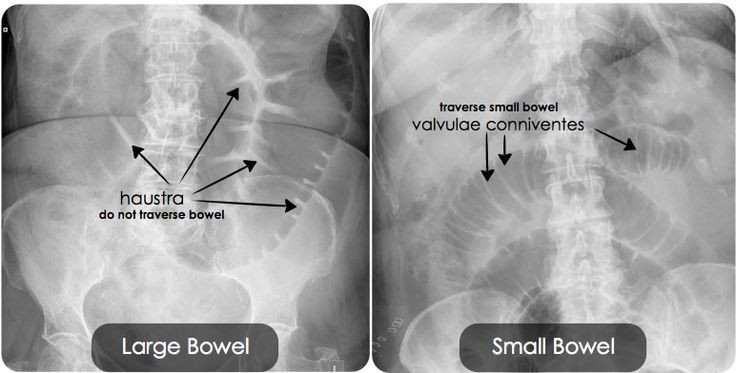

How can you distinguish the small bowel?

Mucosal folds = valvulae conniventes - seen across full width of bowel

How can you distinguish the large bowel?

Pouches that protrude into lumen = haustra

What are the spaces in between the haustra called?

Plicae semilunaris